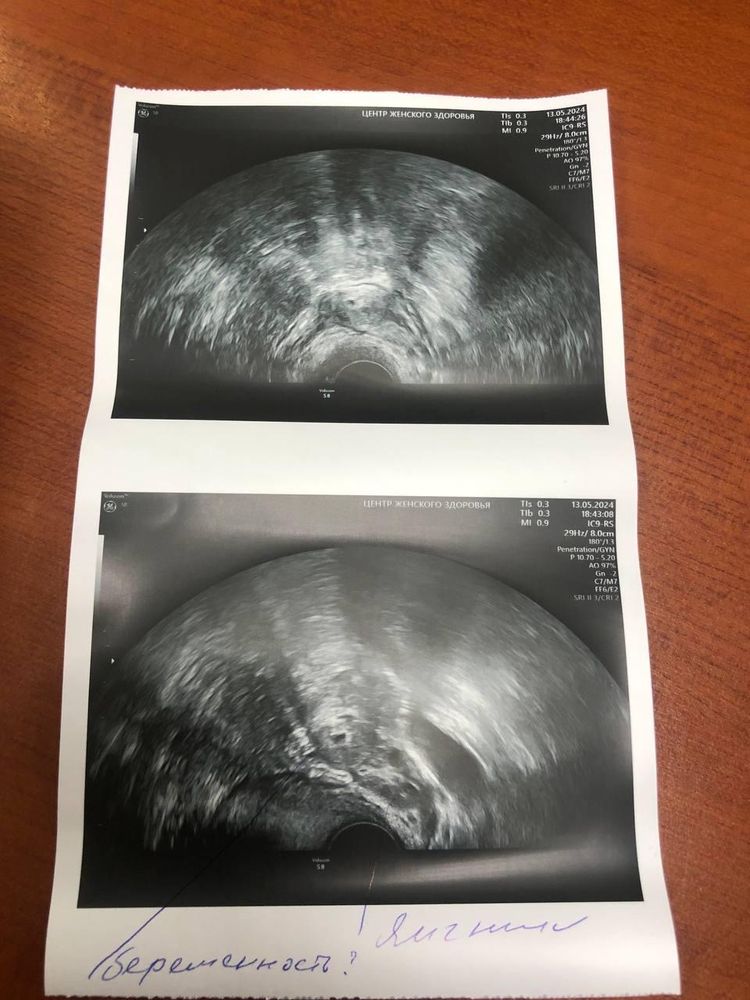

Kris Ivanova, так я еще просто не понимаю что это вообще было то? На 4 неделе ведь уже плодное яйцо можно увидеть,как мне сказали,а у меня слева было лишь образование с единичным кровотоком. Ну и всё обошлось без операций,просто хгч упал,пошли месячные и всё. По сей день все нормально,цикл стабильный. Запугали тогда этой внематочной не на шутку.

Ирина , вы же понимаете, что «образование 17х11мм» само из трубы не рассосется? А куда оно делось у вас?

Вам нужно проверить трубы и сделать узи эксперт класса... По моим предположениям беременность была трубной, не увидели сначала потому что маленькое плодное яйцо было, чуть позже подросло и увидели... Скорее всего замерло в развитии, поэтому упал хгч и ушла жидкость... Неужели вы успокоились и больше не ходили на узи? Я после ЗБ в июне каждый цикл хожу, чтобы убедиться что все хорошо... А тут такое...

Ну есть вариант той же ЗБ, но в трубе с дальнейшим самопроизвольным абортом. Почему все считают, что из матки ПЯ может само выйти, а их трубы нет? Так же точно замерла Б, реснички трубы вынесли отвалившееся ПЯ в матку и далее на выход. Тут вообще все уверены, что если поймали БХБ, то значит трубы проходимы ибо она априори маточная. Нет, она могла быть и на Я, и в печени, и в брюшине, и в трубе, и просто перестала развиваться. Спермии могут протиснуться в просвет трубы, а ЯК уже нет. Может у вас оно и не вышло с М, а просто рассосалось в брюшине. Вариантов масса - вам правильно советуют проверить трубы на проходимость. И пусть следующая Б будет удачной!

Есть же вариация трубного аборта. В дальнейшем рекомендуется контроль узи и гсг для того, что бы труба была проходима.

При хгч 1000 ПЯ вряд ли увидят даже в трубе. Вам нужно сделать гсг маточных труб и узнаете проходимы они или нет. А так это гадание на кофейной гуще